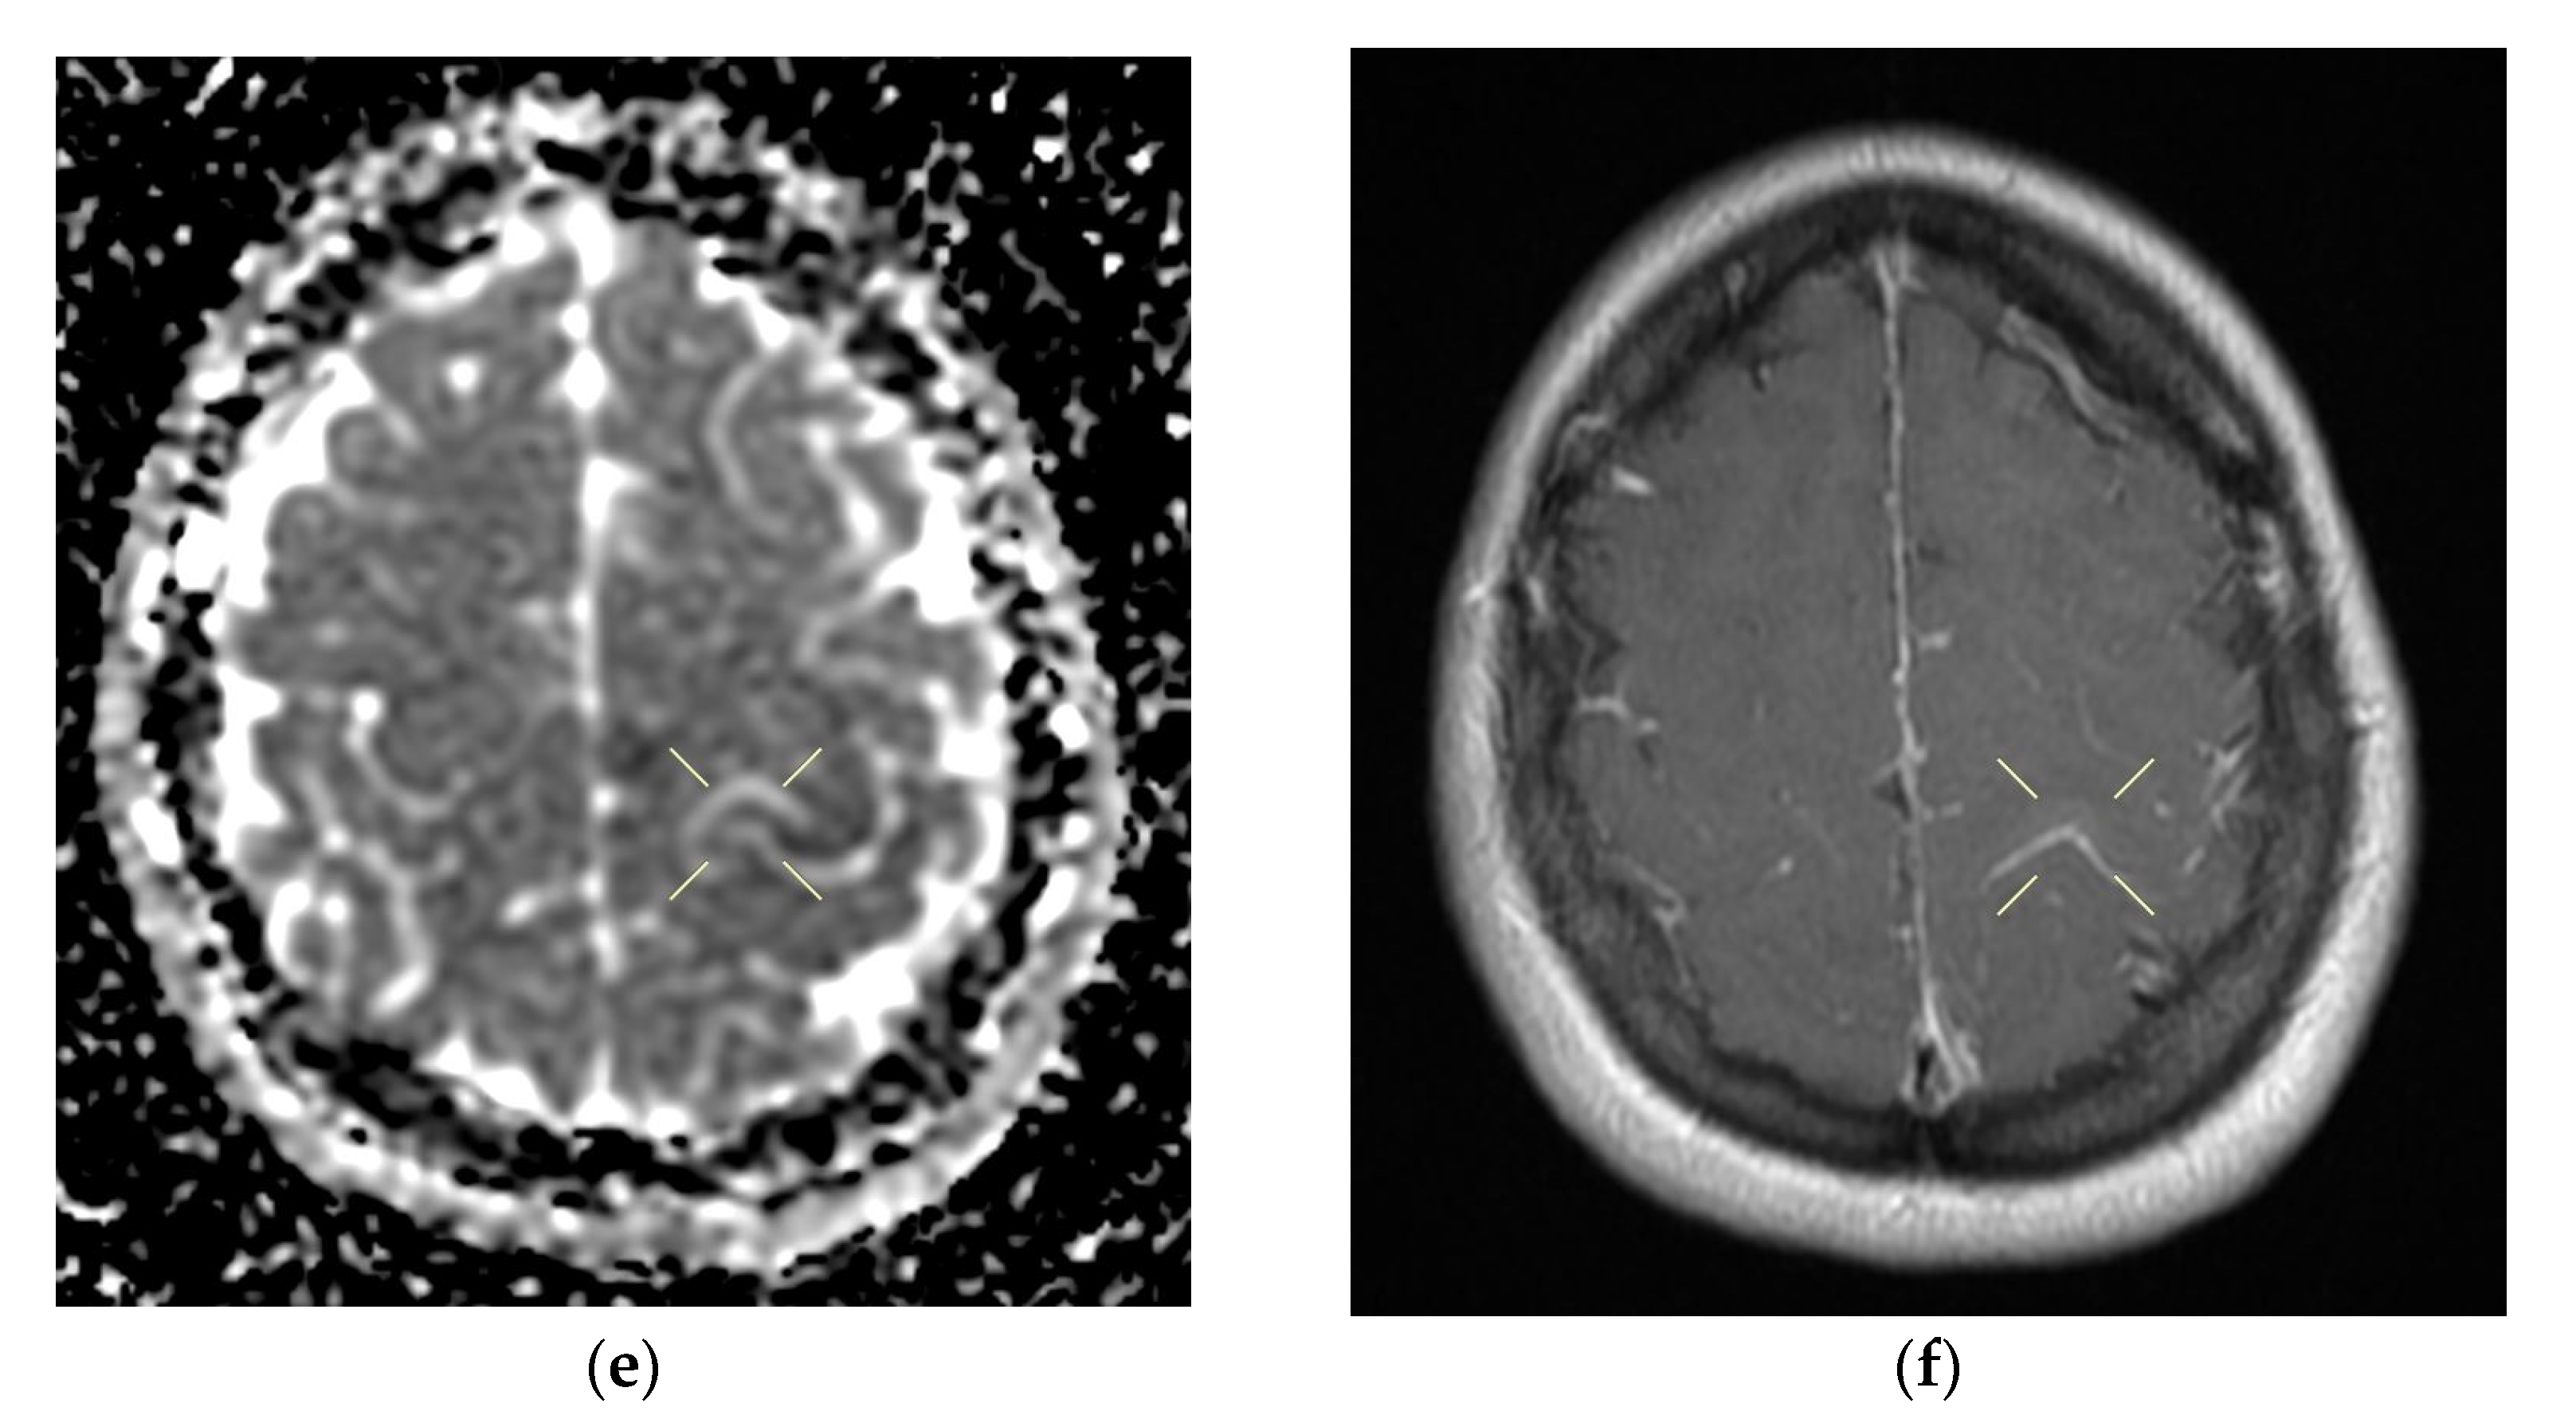

Figure 2. Cerebral native and contrast-enhanced MRI and angiography, and CT cerebral venography highlighting the sigmoid sinus and right lateral sinus thrombosis and the inferior sagittal sinus and right sinus thrombosis, associated with right temporal cortical and subcortical subacute hemorrhage, supratentorial recent subacute synchronous lacunar infarct, (cytotoxic and vasogenic) thalamic–lenticular–caudal edema, and supratentorial non-specific demyelinating lesions. Magnetic resonance imaging shows cortico-subcortical subacute hemorrhage in the right temporal lobe (a,b) T1 and T2 hyperintensities. (c) methemoglobin signal. (d) heterogeneous contrast enhancement. (e) supratentorial recent subacute lacunar infarction in a millimeter lesion in hypersignal FLAIR, restrictive in diffusion coefficient. (f,g) supratentorial recent subacute lacunar infarction located in the corpus callosum. (h,i,j,k) cytotoxic and vasogenic edema in diffuse T2 and FLAIR high signal and moderate restriction in diffusion coefficient in the left thalamus. (l,m,n,o) cytotoxic and vasogenic edema in left lenticular-caudate nucleus. (p) right sigmoid and lateral sinuses thrombosis—T1 and T2 hyperintense material, without contrast enhancement. The intravenous post-contrast and native cranio-cerebral MRI examination highlights are as follows: oval globular formations with a non-homogeneous central portion and a periphery with a methemoglobin signal, hyper-intense T1–T2, axial dimensions of 11/10 mm maximally and heterogeneous contrast outlet, along with right temporal cortical and subcortical conglomerates, with extended moderate perilesional oedema; FLAIR hyper-intense millimeter lesions, intense and homogeneous restriction in diffusion and no-contrast outlets in the semioval centers, in the corpus callosum and in the middle temporal gyrus; diffuse signal T2–FLAIR increased in the left and left lenticular–caudal thalamus, with minimum diffusion restriction and no detectable contrast outlets; a few T2–FLAIR hyper-signal millimeter outbreaks, with no diffusion restriction and no corresponding T1, located in the white matter in the periventricular hemisphere and bilateral frontal–parietal subcortical area; normal supra- and infratentorial pericerebral liquid spaces; a symmetric ventricular system, with normal dimensions; structures of the median line in normal position; orbits and orbital content without anomalies; and paranasal sinuses with normal development and pneumatization. Magnetic resonance (MR) cerebral arteriography and venography indicated the following: internal carotid arteries symmetrically disposed, with a normal trajectory and caliber; anterior cerebral arteries and normal average bilaterally detached from the internal carotid, with no areas of stenosis or circumscribed dilation, with a homogeneous intralumenal signal; vertebral arteries, basilar artery, upper cerebral arteries and communicating arteries with a normal trajectory and caliber; hyper-intense T1–T2 material, with a no-contrast outlet, which transversely occupied the sinuses and sigmoid on the right side; and a lesion with the same signal characteristics situated along the right sinus and extended towards the inferior sagittal sinus; the rest of the dural sinuses had no detectable lesions in the sequences observed.